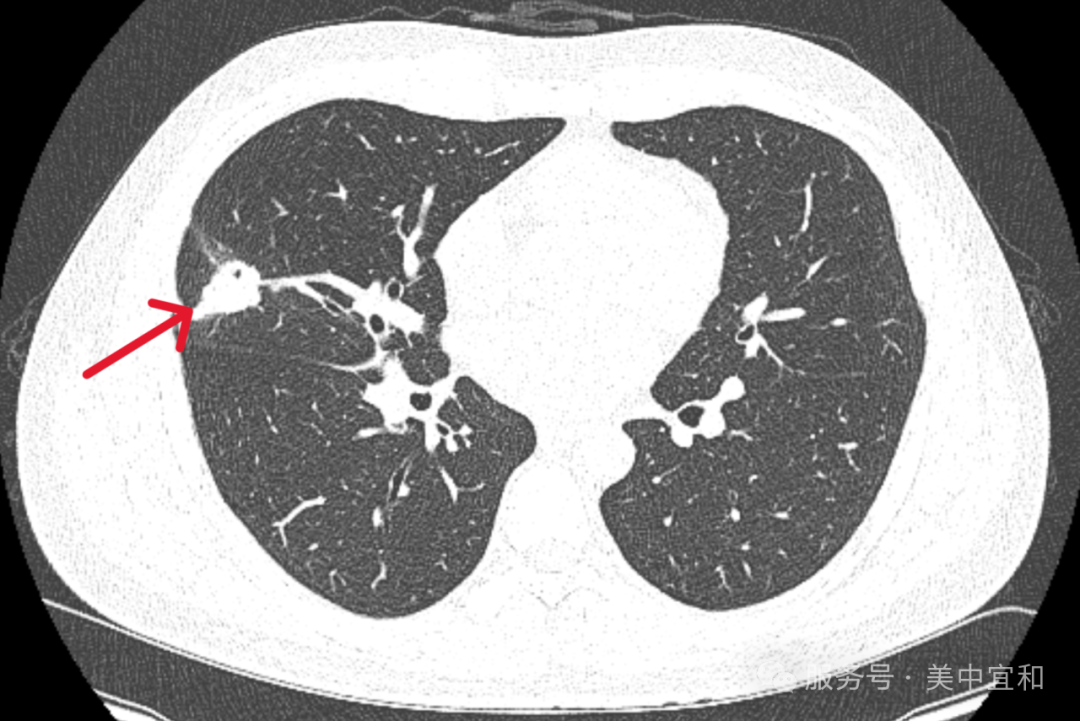

CT 检查结果显示 Z 先生 右肺中叶外侧段占位累及邻近胸膜占位,约 30×20 mm,C-Lung-RADS 4 级,肿瘤标记物癌胚抗原 CEA 及鳞状细胞相关抗原均增高。

对于这个意外诊断,Z 先生起初不敢相信,但在进一步诊断后,明确为肺交界性肿瘤——指生物学特征介于良性肿瘤和恶性肿瘤之间的肺部病变,属于一种潜在低度恶性或不确定恶性潜能的肿瘤类型。简单来说:肺交界性肿瘤是 「肿瘤进展的中间状态」—— 它比良性肿瘤 「危险」(有进展和复发可能),但比恶性肺癌 「温和」(无转移能力,规范治疗后预后较好)。